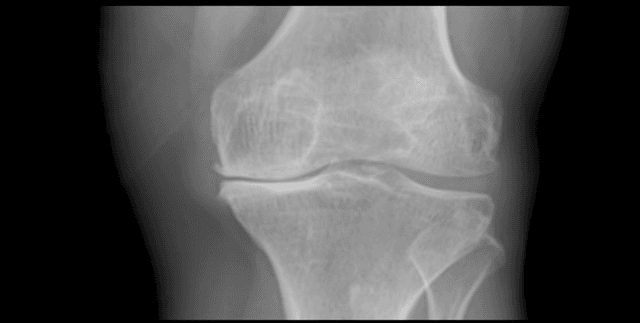

This curated dataset features 1,650 high-quality digital X-ray images of knee joints, meticulously sourced from leading hospitals and diagnostic centres. The collection is designed to accelerate the development of automated diagnostic tools for knee osteoarthritis (OA), a condition impacting millions globally where accurate diagnosis is crucial for successful treatment. Each image is expertly labeled using the Kellgren and Lawrence (K&L) grading system, recognised as the gold standard for assessing OA severity through radiographic features. This robust, labeled collection allows researchers to merge medicine and technology for improved health outcomes.

The dataset consists of 1,650 digital knee X-ray image files. These images are captured in grayscale and have an 8-bit depth, having been processed using a PROTEC PRS 500E X-ray machine. The data is organised within a main directory containing all 1,650 image files. Expert annotations, specifically the K&L grades labeled by two medical professionals, are provided either embedded within the filenames or within a separate metadata file, such as a CSV or text file. The accompanying CSV metadata file is 330 B in size.

The data focuses exclusively on digital X-ray images of the knee joint. The data was sourced from top hospitals and diagnostic centres. This work was brought forth by Rani Channamma University, located in India.